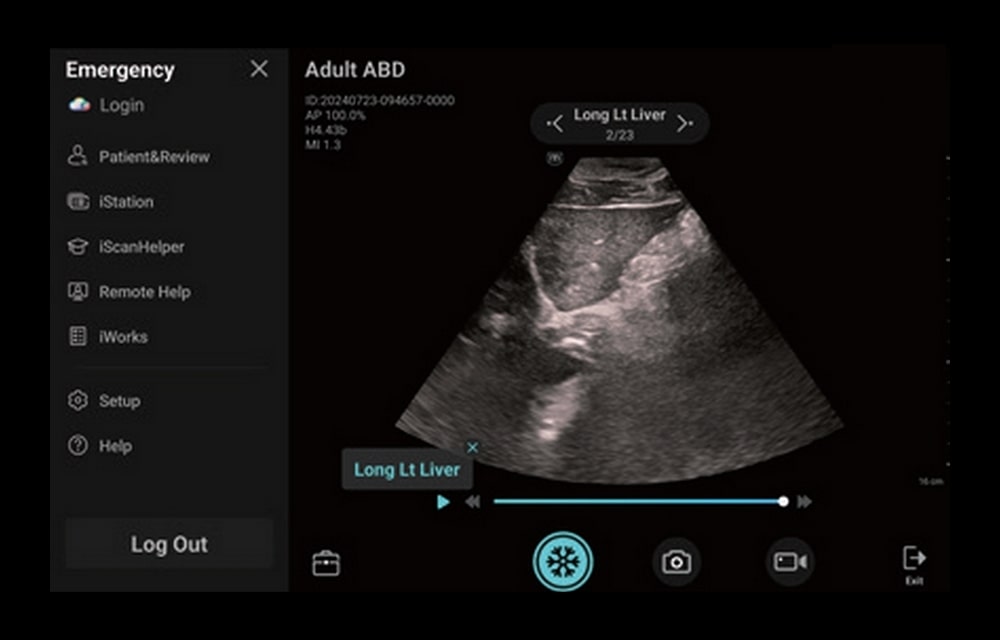

L’ecografo palmare TE Air, rappresenta oggi il Top tra gli ecografi portatili. Il trasduttore collegato ad uno smartphone o ad un tablet in modalità Wifi, garantisce prestazioni full body di qualità superiore alla media degli ecografi ultraportatili. Consente l’uso, in emergenza, di applicazioni diverse.

TE Air grazie alle sue dimensioni ed al peso ridotto è perfetto per uso mobile ed a domicilio del paziente. L’ecografo palmare è molto semplice nel suo utilizzo e pronto all’uso in pochi secondi. La durata della batteria interna garantisce un’autonomia di lavoro superiore all’ora e mezza ed il tempo di ricarica è di soli trentacinque minuti. Facile da pulire, con superficie resistente ai disinfettanti per un impiego igienico. TE Air e5M è in grado di gestire la scansione dell’intero corpo e di adattarsi a vari scenari clinici. Il suo design wireless consente esami ecografici di alta qualità in qualsiasi momento e ovunque. Oltre alla sua versatilità, TE Air e5M offre anche una gamma di funzioni intelligenti e strumenti didattici per aumentare la sicurezza e l’efficienza.